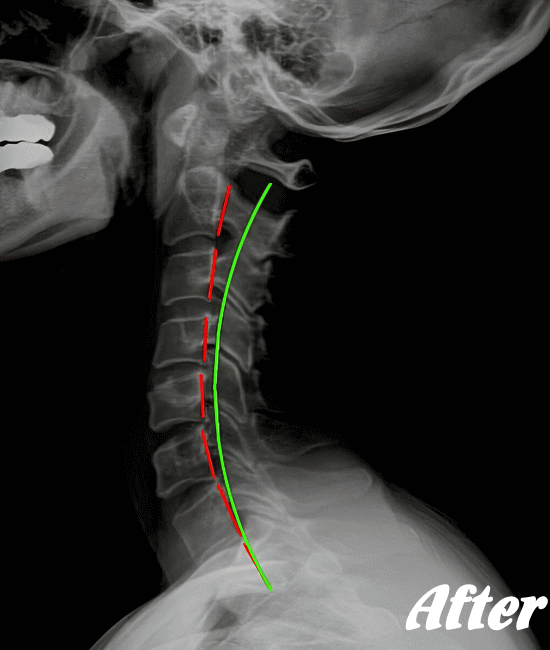

ストレートネックも、首に負担がかかりやすいので、注意が必要です。

HALOカイロプラクティック☆平和島整体院では、首の筋肉をゆるめていくため、まずは骨盤(特に仙腸関節)を調整、背骨(腰椎、胸椎、頚椎)を調整、そして肩甲胸郭を調整します。

そして、肩甲胸郭、つまり肩甲骨の動きをよくし、肋骨を広げ、丸まった背をのばし、胸が大きく広がるように調整します。肩甲骨には首の筋肉がつながっているので、調整は必須です。

状態に応じて、頭蓋骨を調整し、身体をリラックスさせます。基本的に、頚性神経筋症候群は姿勢の悪さに起因するところが大きいので、深く呼吸できる身体に改善していくことで、首のコリは取れていきます。